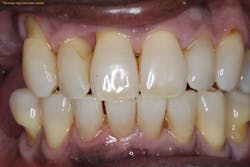

While studies have shown that these services are effective, sometimes there are cases where a patient returns for a periodontal maintenance appointment within eight to 12 weeks of periodontal therapy with unresponsive tissues. When biofilm is still present and periodontal disease is still active, dental professionals may feel at a loss as to what other treatment they could offer their patients. Now, thanks to advancements in technology, dental professionals can use periodontal desiccation to help to ensure a better outcome with periodontal treatment.

Periodontal desiccation offers many benefits to the patient and clinician. The process of periodontal desiccation works by drying out the plaque biofilm and the necrotic tissue that could remain after periodontal scaling and root planing.2 Once the biofilm matrix is dry, it can no longer remain attached to the tooth’s surface, so it is flushed out of the periodontal pocket. This benefits the patient by reducing the high counts of microorganisms in this localized area.2